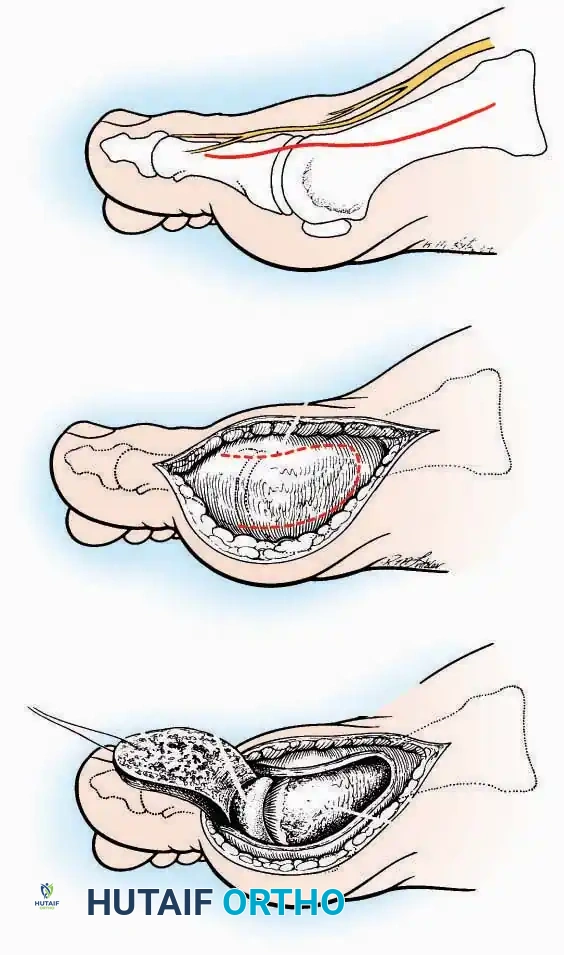

Approaches to the Interphalangeal (IP) Joints

Indications: Arthrodesis for hammer toe deformities, excision of intra-articular osteophytes, or reduction of irreducible dislocations.

Surgical Technique:

* Great Toe: Make a 2.5 cm longitudinal incision strictly on the medial midaxial aspect of the toe.

* Fifth Toe: Utilize a lateral midaxial incision to avoid interdigital maceration.

* Lesser Toes (2nd, 3rd, 4th): Approach the IP joints through a dorsal longitudinal incision placed just lateral to the corresponding extensor digitorum longus (EDL) tendon.

* Deep Dissection: Carry the dissection sharply through the subcutaneous tissue and superficial fascia directly to the joint capsule.

* Neurovascular Protection: Reflect the skin edges with meticulous care. Retract the dorsal digital nerves and vessels dorsally, and the plantar nerves and vessels plantarward.

* Capsulotomy: Open the capsule either transversely (for joint resection/arthrodesis) or longitudinally (for exploration), exposing the articular surfaces.